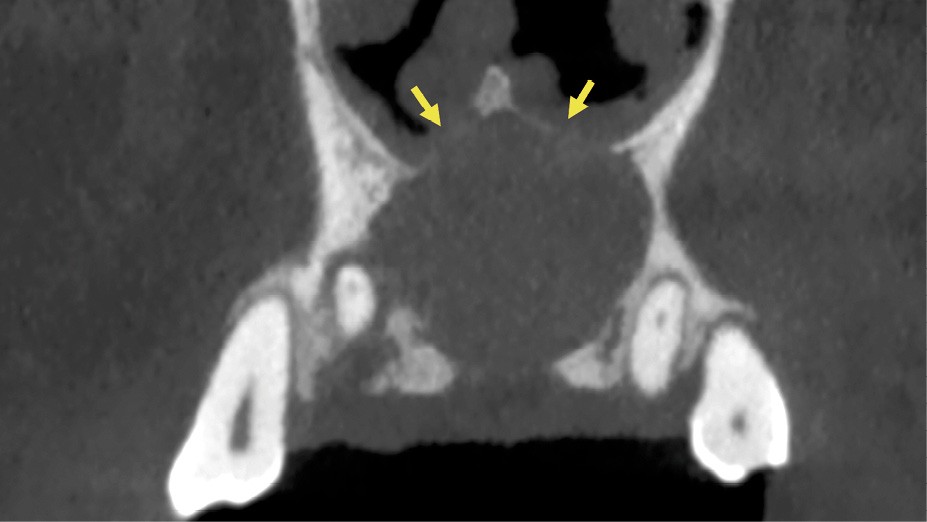

- Centré sur la ligne médiane de la portion antérieure du palais.

- Lésion ostéolytique radio-claire.

- Homogène et bien délimitée.

- Uni-loculaire (fig. 3), pouvant présenter un aspect caractéristique de « cœur de carte à jouer ».

- Diamètre moyen des lésions de 2 cm.